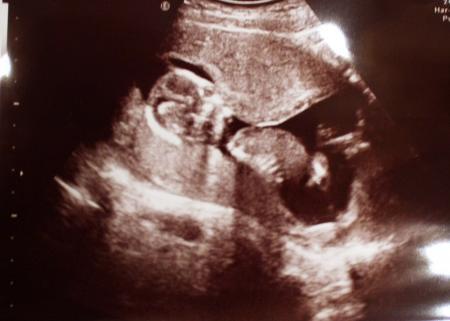

Hallöchen, wir waren heute Nachmittag zur Kontrolle mit zusätzlichem Wunsch-US. Schließlich wollte der werdende Papa auch mal den Zwerg sehen. Die Ärztin hatte sich wirklich viel Zeit genommen. Anfangs schlief unser Kleines, tiefenentspannt wie ein Yogi im Schneidersitz, dann wurde es wach, kratzte sich am Ohr, strampelte und winkte uns zu. 3 bis 5 Mal versuchte die Ärztin, einen Blick zwischen die Beine zu erhaschen, aber jedes Mal kreuzte es die Beinchen. Es will uns noch etwas auf die Folter spannen. Aber das wichtigste: alles ist in Ordnung, Herzchen schlägt, zeitgerecht entwickelt und schon fast 10 cm groß. In 4 Wochen am 23.3. ist der nächste Termin. Habt einen schönen Abend. Glückliche Grüße Jule

hier ist noch ein Foto